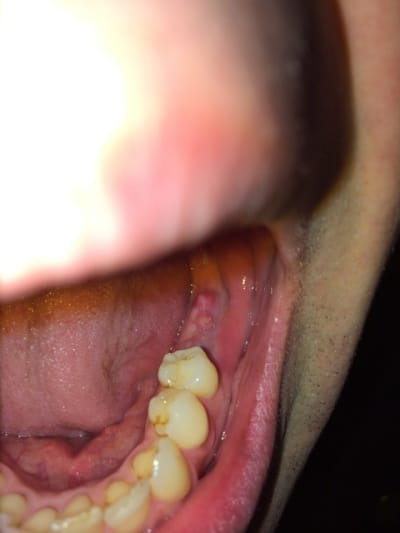

À 5 semaines post op le patient m'envoie une photo et ce n'est pas très beau au niveau gingival, limite pire.

Ci jointes radio post op et à 3 semaines et dernière photo de gencive.

pas joli l'état gingival....:-(

abcès gingival

et puis perso, çà ne me fais absolument pas penser à un abcès gingival...